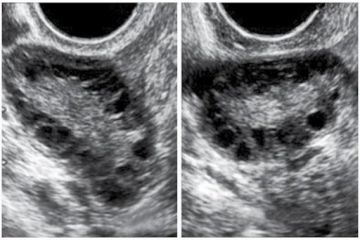

Cập nhật về hình ảnh buồng trứng đa nang trên siêu âm

Thứ Sáu, 15/09/2023Hình ảnh buồng trứng đa nang trên siêu âm (Polycystic Ovary - PCO), nói gắn gọn siêu âm buồng trứng đa nang - được xem là một trong những tiêu chuẩn chẩn đoán hội chứng buồng trứng đa nang.